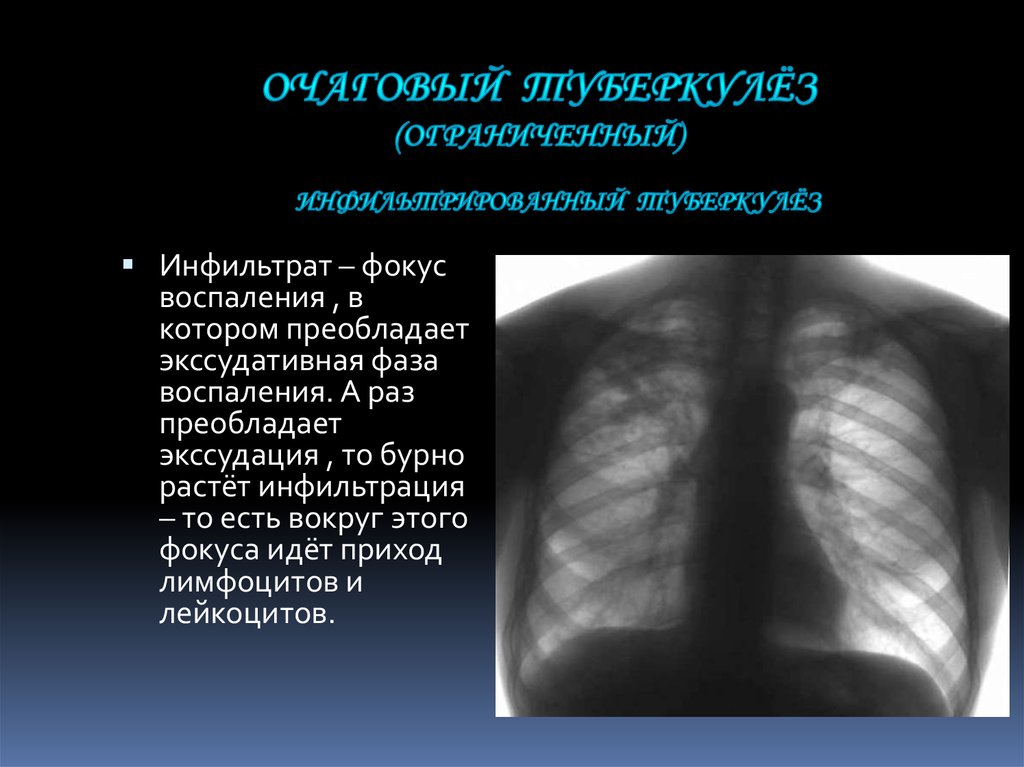

Очаговый и инфильтративный туберкулез презентация - 94 фото